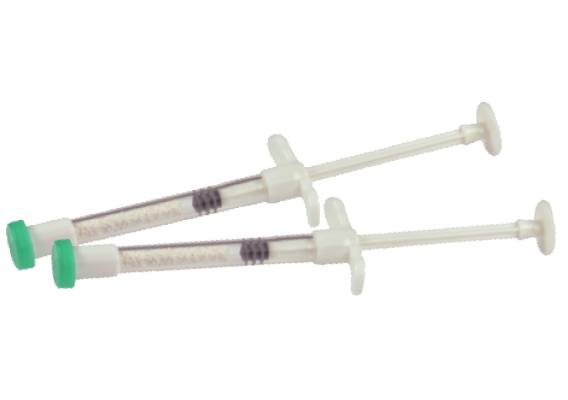

Syringe Type

Syringe Type

Cylinder in syringe

Cylinder in syringe

Straumann® XenoFlex is composed of 90% XenoGraft granules embedded

in 10% purified porcine-derived collagen (type I).

Straumann XenoFlex is an optimal solution for graft applications required

in extraction sockets and is available with a syringe applicator.

in 10% purified porcine-derived collagen (type I).

Straumann XenoFlex is an optimal solution for graft applications required

in extraction sockets and is available with a syringe applicator.

Straumann XenoFlex can be easily cut to match the size and shape of the individual defect after hydration.

Straumann XenoFlex can be placed into the defect in one piece using tweezers, shortening surgery time.

Outstanding product stability after thorough hydration, supporting product application

Straumann XenoFlex can be placed into the defect in one piece using tweezers, shortening surgery time.

Outstanding product stability after thorough hydration, supporting product application

Straumann® XenoFlex is composed of 90% XenoGraft granules embedded

in 10% purified porcine-derived collagen (type I).

Straumann XenoFlex is an optimal solution for graft applications required

in extraction sockets and is available with a syringe applicator.

in 10% purified porcine-derived collagen (type I).

Straumann XenoFlex is an optimal solution for graft applications required

in extraction sockets and is available with a syringe applicator.

Straumann XenoFlex can be easily cut to match the size and shape of the individual defect after hydration.

Straumann XenoFlex can be placed into the defect in one piece using tweezers, shortening surgery time.

Outstanding product stability after thorough hydration, supporting product application

Straumann XenoFlex can be placed into the defect in one piece using tweezers, shortening surgery time.

Outstanding product stability after thorough hydration, supporting product application